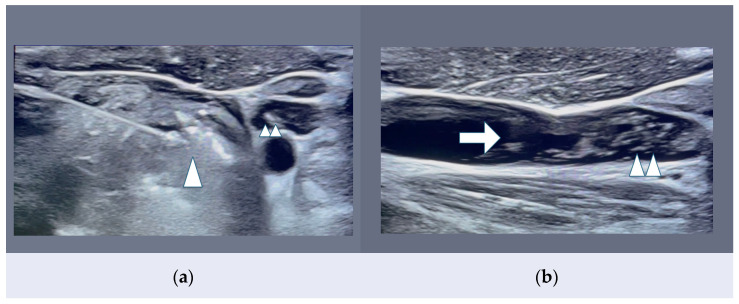

New Trends in Thyroid Malignancy: Minimally Invasive Thermal Ablation Percutaneous Techniques for T1 Papillary Thyroid Carcinomas.

During the late 1990s, thyroid nodule management strongly improved with the development of high-frequency ultrasound (HFUS) and US-guided percutaneous procedures [...].